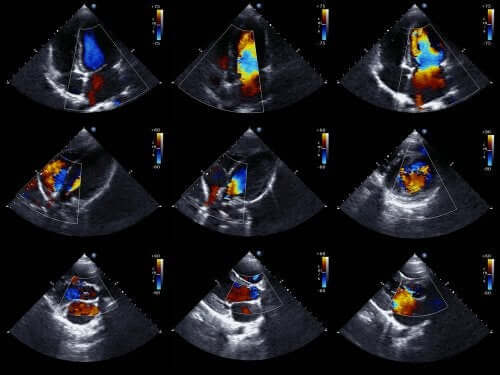

Um ecocardiograma é o exame preferido para detectar o derrame pericárdico. Também é chamado de ecocardiografia ou ultrassonografia cardíaca. É um teste que permite visualizar a estrutura do coração e estudar sua capacidade de bombear o sangue.

O ecocardiograma com Doppler também permite estabelecer a velocidade exata dos fluxos do coração. Do ponto de vista técnico, o ecocardiograma bidimensional e no modo M é a técnica ideal para diagnosticar, quantificar e monitorar o derrame pericárdico.

A ausência de ecos entre o epicárdio e o pericárdio lateral é uma descoberta que permite diagnosticar o derrame pericárdico. O cardiologista determina o tamanho do derrame a partir da quantidade de espaço existente entre as duas camadas do pericárdio.